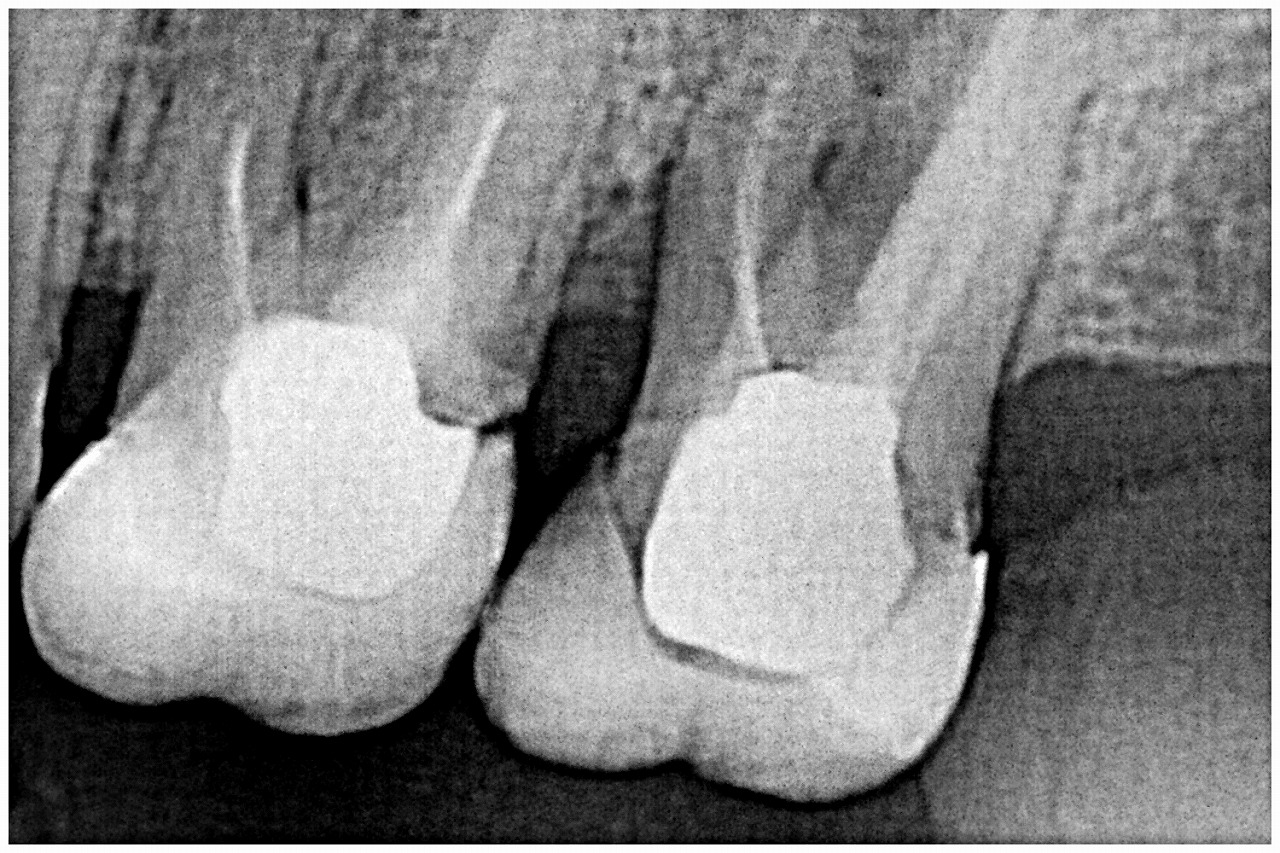

問題の歯になります

割れているのは被せでした

近心根も骨吸収が激しいです

近心部にも破折の疑いの所見が出ています